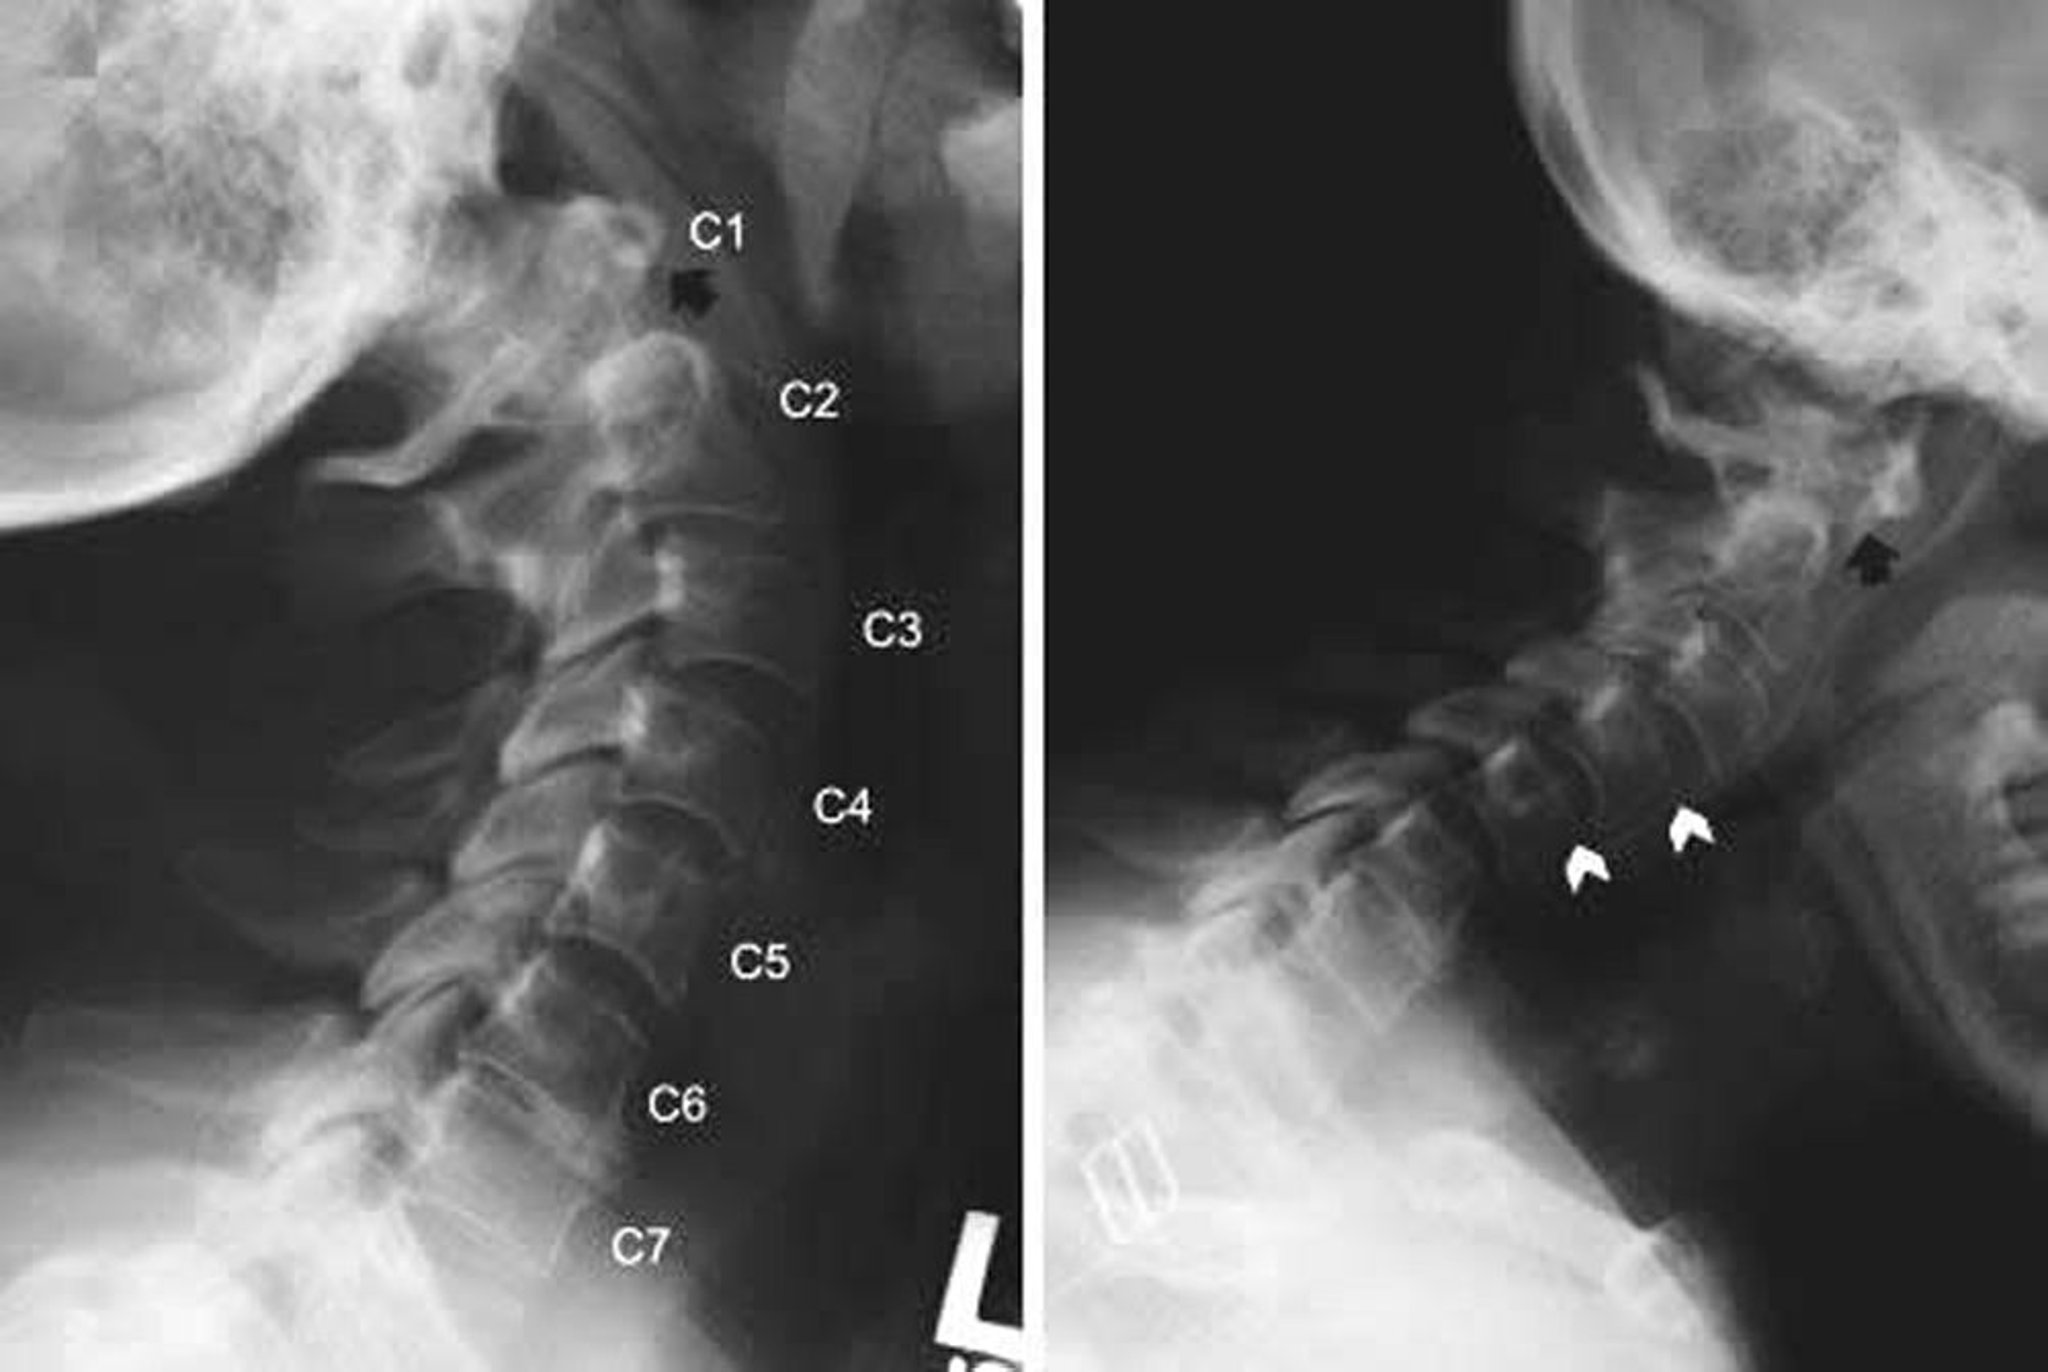

Atlantoaxiale Subluxation

Röntgenaufnahmen der Halswirbelsäule, die atlantoaxiale Subluxation und subaxiale Subluxation bei einem Patienten mit rheumatoider Arthritis zeigen. Die Seitenansichten der Halswirbelsäule wurden bei Halsverlängerung (links) und Flexion (rechts) aufgenommen. In der Flexion liegt der vordere Bogen von C1 weit vor den Höhlen von C2 (hinter dem schwarzen Pfeil), was auf eine anteriore Subluxation hinweist. Dieser Befund ist in der Verlängerung nicht erkennbar (schwarzer Pfeil), was anzeigt, dass die atlantoaxiale Subluxation dynamisch ist. Anterolisthesis (Gleiten des oberen Wirbelkörpers nach vorne, dargestellt durch weiße Pfeilspitzen) ist auch bei C2-C3 und C3-C4 in Extension und bei C3-C4 und C4-C5 in Flexion vorhanden.